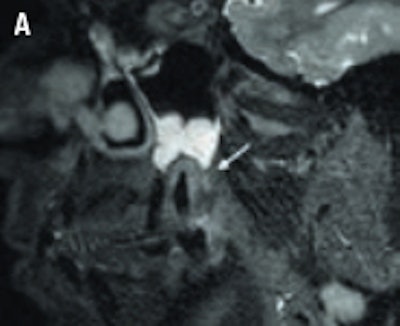

An example of cone-beam CT. In this instance, the lower left third molar (d. 38) was imaged after panoramic radiograph with CBCT. The arrows mark the mandibular canal. Images courtesy of Dr. Anni Suomalainen.